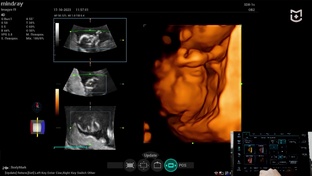

18:061,0×00:00/18:06ПодборкаMEDLIGA - поставка медицинского оборудования137 смотрели · 1 год назадПодписатьсяУЗИ общего профиля на аппарате для акушерства и гинекологии Mindray Imagyn i9